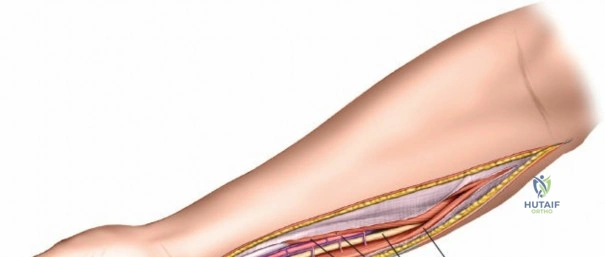

Superficial Surgical Dissection and Internervous Plane

Incise the deep fascia of the forearm in line with the skin incision. The initial goal is to identify the medial border of the brachioradialis as it courses down the forearm. It is a common pitfall to search for this border too far laterally. At the level of the elbow, the brachioradialis is expansive and extends almost halfway across the anterior forearm. It is surprisingly easy to mistake the plane between the brachioradialis and the extensor carpi radialis longus for the correct intermuscular plane.

To confirm the correct plane, look for the superficial branch of the radial nerve. This sensory nerve runs on the undersurface of the brachioradialis muscle. Once the true medial edge of the brachioradialis is found, develop the plane between it and the pronator teres (proximally) or the flexor carpi radialis (distally). Retract the brachioradialis laterally, taking care to keep the superficial radial nerve attached to its undersurface to protect it from traction injury.

Managing the Radial Artery and Recurrent Leash

As the brachioradialis is retracted laterally, the radial artery and its venae comitantes are exposed lying deep in the middle part of the forearm, closely related to the medial edge of the wound. Begin dissection distally and work proximally. Just below the elbow joint, the radial artery gives off the recurrent radial artery and a leash of muscular branches that dive laterally into the brachioradialis.

This leash must be meticulously managed. Take time to isolate, ligate, and divide these vessels. Do not attempt to use electrocautery alone on the larger branches, and absolutely avoid blunt avulsion. Avulsion of these vessels from the main radial artery is a potent cause of difficult-to-control intraoperative bleeding and severe postoperative hematoma. Once the leash is divided, the brachioradialis can be fully mobilized laterally, exposing the deep muscular layer.